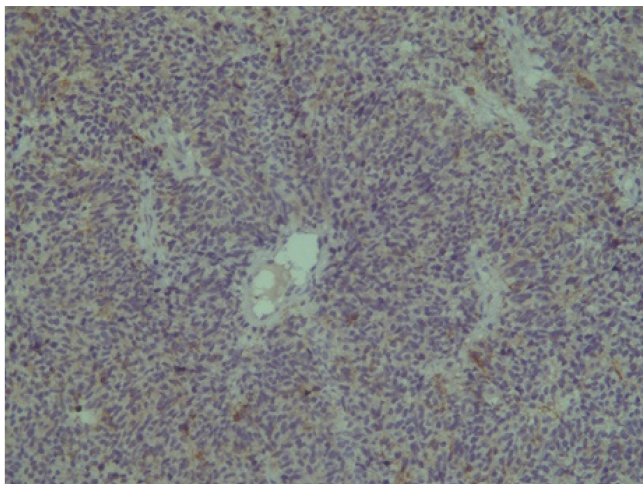

Поэтому при первичном гистологическом исследовании диагноз эстезионейробластомы был установлен только у 6 пациентов (66,6 %), у троих больных (33,4 %) были диагностированы другие формы злокачественного процесса, что не соответствовало клиническим проявлениям. Во всех случаях проводили иммуногистохимическое (ИГХ) исследование. ИГХ-исследование проводили на срезах с парафиновых блоков с использованием антител к Keratin.Pan (AE/AE3), CD45 (Cocktail), Synaptophysin (SP11), ChromograninA (SP12), CD56 (56C04), Ki-67 (30-9), p63 (7JUL)RTU, S100, INI1, CD99 (HO36-1.1). Также выполняли доставку с антителами к EMA (E29), TTF1 (8G7G3/1). В диагностических материалах была отмечена положительная экспрессия Synaptophysin, ChromograninA, CD56, Ki-67 (до 90% ядер), INI1 (рис. 2–6).

Отрицательная экспрессия была отмечена в диагностических образцах с использованием антител к Keratin.Pan, CD45, p63, S100, EMA (E29), TTF1(рис. 7–12).

Рис. 4. CD 56 [56C04] ×200

Рис. 5. Ki-67 [30-9] (90%) ×200

Эти результаты иммуногистохимического исследования подтверждают наибольшее соответствие иммунофенотипа опухоли – ольфакторной нейробластоме (G3 по Hyams) М9522/33.